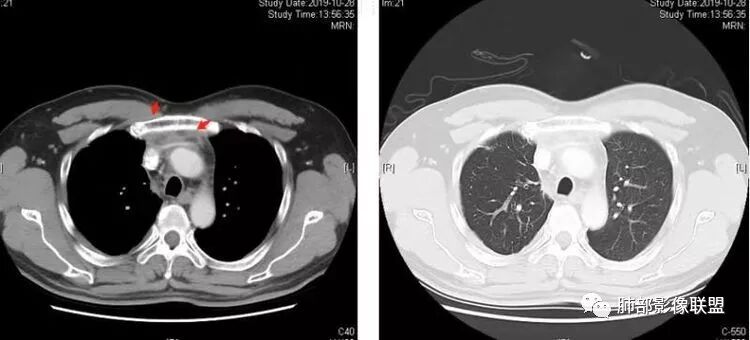

大家仔细看看积液中的游离气体;

不是支气管,是积气;是穿刺进去的;

囊内密度不一致

我认为囊张力高,积液中的气体均在周围,外侧、下方,囊内有间隔:各腔密度不一致;提示:囊腔属于前纵隔,不是包裹性积液;现在的问题:囊腔与内侧的病灶是否是一体的